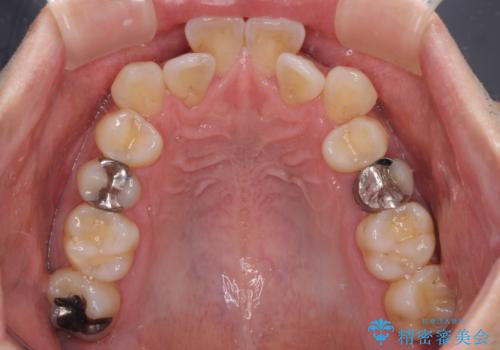

- 前歯のクロスバイトを改善したいとのことで来院された患者様です。

マウスピース矯正では前歯の神経への負担が大きいことを懸念され、ワイヤー装置による矯正治療を行うこととしました。

舌の突出癖が認められたため、デコボコ改善に伴い前歯が前突する可能性があったため、舌のトレーニングをしっかりと行うよう指導しながら治療を進めることとしました。

舌の突出癖の影響か、下顎前歯がなかなか整わず、治療期間は予定よりも長期間となりました。

舌突出癖改善のトレーニングの重要性を認識することとなりました。